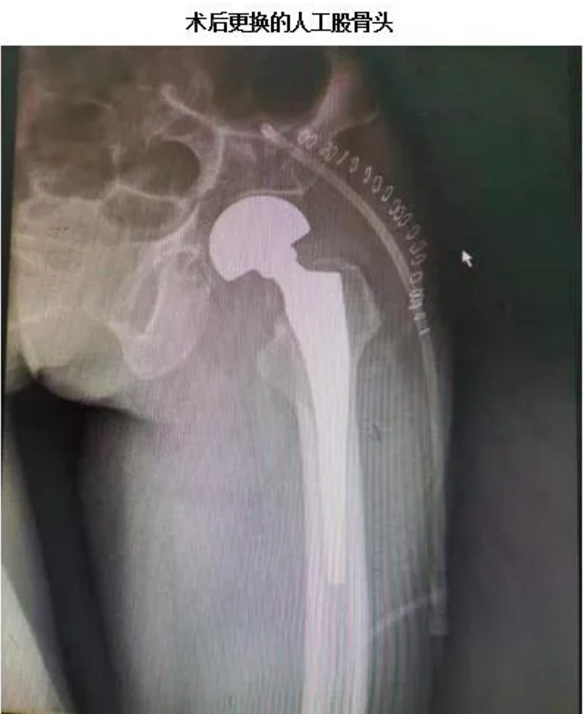

不久前,红河州第三人民医院骨科再次完成一例高龄老人“人工股骨头置换术”。患者许某某今年92岁,11月18日因为不慎摔倒,“左侧股骨颈骨折”收住红河州第三人民医院骨科治疗,经骨科赵林主任及周源主治医师评估及制定手术方案,择期为患者进行了“左侧人工股骨头置换术”,2020年12月10日,患者的患肢恢复情况及伤口愈合良好予以出院,目前,现者已可以在助行器辅助下缓慢行走。

红河州第三人民医院骨科已成功开展高龄老年人人工股骨头置换术多例,年龄最大者100岁,手术技术成熟、成功率高,适用于高龄股骨头、颈粉碎性骨折患者,陈旧性股骨颈骨折不愈合患者,股骨头部良性肿瘤不宜行刮除植骨者,对于恶性转移性肿瘤股骨颈病理骨折,为减轻病人痛苦,也可行人工股骨头置换术。假体置入人体后,其抗磨损能力大约为10至15年,而老年人患者由于活动频率较小,且受力强度低,一般可维持10至20年,甚至更长时间。因此,对于一些年龄超过50岁的中老年人老说,在进行人工股骨头置换术后,再配合一些措施,假体基本上可以维持一生。